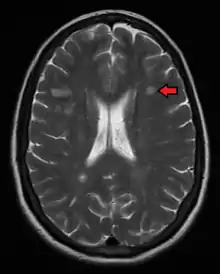

Magnetic resonance imaging (MRI) of the brain and spine may show areas of demyelination (lesions or plaques). Gadolinium can be administered intravenously as a contrast agent to highlight active plaques, and by elimination, demonstrate the existence of historical lesions not associated with symptoms at the moment of the evaluation.[72][73]

Central vein signs (CVSs) have been proposed as a good indicator of MS in comparison with other conditions causing white lesions.[74][75][76][77] One small study found fewer CVSs in older and hypertensive people.[78] Further research on CVS as a biomarker for MS is ongoing.[79]